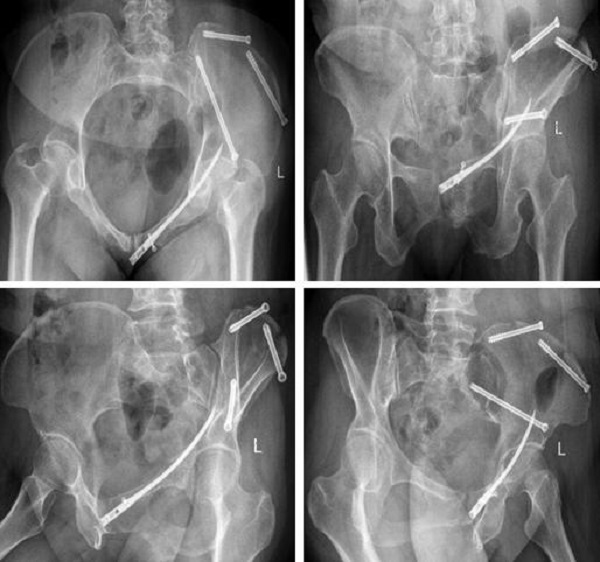

术后复查:

术前,创伤骨科郭永良主任医师团队应用MIMICS软件重建患者骨盆LC—II通道螺钉方向和长度,术中郭永良主任亲自主刀,使用Schanz针协助闭合复位,结合术前模拟通道螺钉方向精确制导,以最小的创伤将LC-Ⅱ通道螺钉顺利置入合适位置,而且完美避开神经及血管损伤,仅通过3枚螺钉使骨盆LC—II型骨折得到有效的稳定固定。